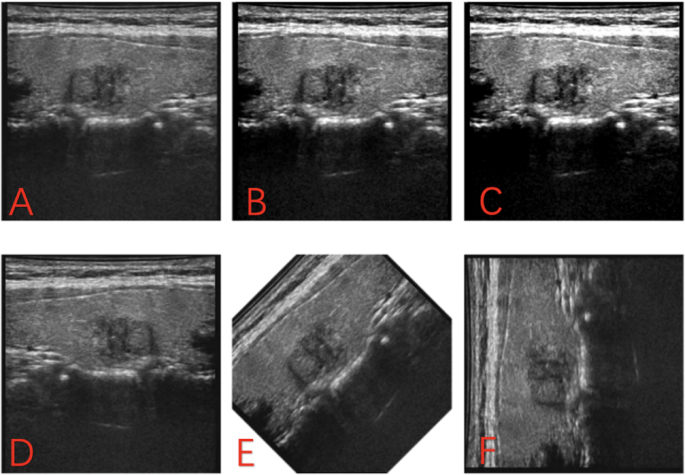

Initially, the original images were converted to grayscale (Fig. 1A), followed by amplification through contrast enhancement (1.5 × and 2x) (Fig. 1B,C), inversion (Fig. 1D), and rotations (45° and 90°) (Fig. 1E,F) to mitigate the effects of insufficient and unbalanced datasets on the predictive model. Various filters were applied to the amplified image data, including Laplacian of Gaussian (LoG, σ = 1, 3), Wavelet (binWidth = 10, 20), Square, Square Root, Exponential, and Gradient filters, to extract the most pertinent features across different scales. Using open source software pyradiomic (v3.0.1, https://github.com/Radiomics/pyradiomics.) in ultrasound images has been drawing ROI extraction of image characteristics of radiomics.

(A): The original images were converted to grayscale. (B) Amplification through contrast enhancement (1.5x). (C) Amplification through contrast enhancement (2.0x). (D) Amplification through inversion. (E) Amplification through inversion rotations (45°). (F) Amplification through inversion rotations (90°).